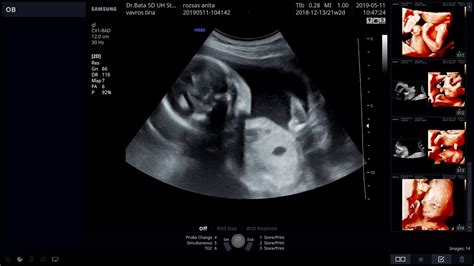

A meddőségi diagnosztikában kiemelt szerepet kapnak a speciális ultrahang vizsgálatok:

- OvaScreen: Egy kifejezetten termékenységre irányuló ultrahang vizsgálat, mely elsősorban a petefészkek állapotára fókuszál. A petefészkek aktuális állapotfelmérésére szolgál, melyből következtethetünk a petefészkek tartalékaira.

- 3D UH: Fájdalommentes hüvelyi ultrahang technika, mellyel a méh üreg alakját vizsgálják. Megmutatja a méhüreg esetleges formai eltéréseit, fejlődési rendellenességeit (pl. sövény, osztott méhüreg). A méhüregben látott szabálytalanságok állhatnak a meddőség, vagy sikertelen meddőségi kezelés hátterében.

- 2D SIS UH: A méh üregét fiziológiás sóoldattal történő feltöltését követő hüvelyi ultrahang technika, mellyel a méh üreg falának eltéréseit vizsgálják. Megmutatja a méhfal összenövéseit (Asherman syndroma).

- 3D SIS UH ("Virtuális hysteroscopia"): A méhüreg 3 dimenziós leképezése fiziológiás sóoldattal történő feltöltést követően. Ezzel a technikával az esetlegesen előforduló myomák pontos helyzetét is meg lehet ítélni.